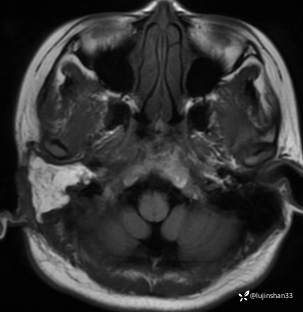

颞骨MRI:

临床诊断:1.右侧岩部胆脂瘤 2.外耳道耵聍癌术后(右)